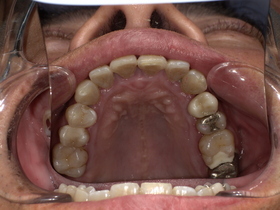

症例結果|Before / After

After

- 自然な白さ

- 違和感ゼロ

- 美しく機能的

👉 見た目も機能も大きく改善

治療詳細

- 年齢:50代男性

- 期間:約2週間(2回)

- 費用:セラミックジルコニア冠198,000円(税込)

土台 44,000円(税込)